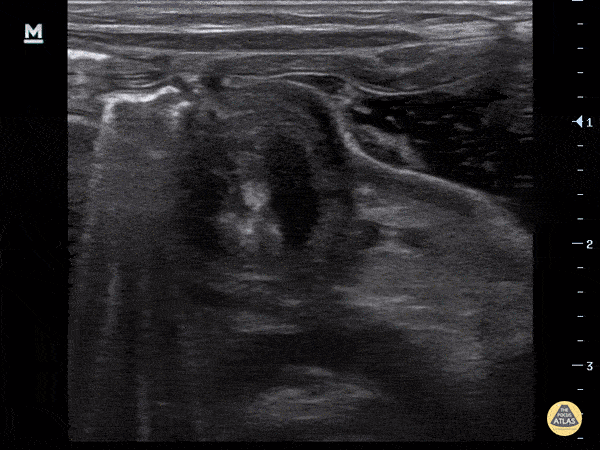

Peds-Gastrointestinal - Pyloric Stenosis (Transverse)

4-week-old, vomiting intermittently for 2 weeks, seen PCP 3 days ago, reassured. Revisit today and PCP concerned for pyloric stenosis, so referred to ED. Exam in ED reassuring for well-appearing neonate. In ED, POCUS completed revealing hypertrophic pyloric stenosis. Pylorus muscle hypertrophied and thickened in both transverse and logitudinal view. Transverse view demonstrates the classic target sign seen in pyloric stenosis. Dr. Sathya Subramaniam, Pediatric EM Fellow - Kings County/SUNY Downstate